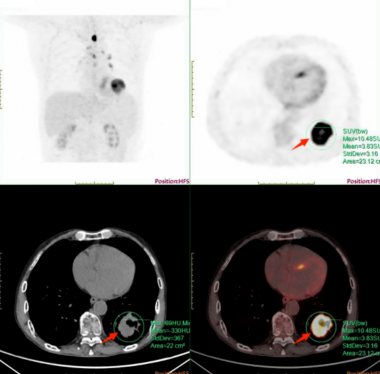

医学领域

更多>

MRI兼容的高性能PET研究及医学应用——中国科学院深圳先进技术研究院研究员柳正